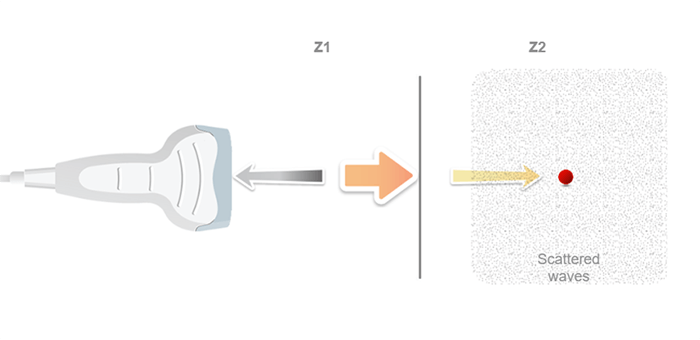

An ultrasound probe emits a pulse in response to electrical excitation. This ultrasonic pulse, transmitted to biological tissues, spreads by degrees.

The echoes are generated by reflection or scattering and propagate backward towards the probe, which operates in receiver mode immediately after the pulse is transmitted. Whenever an echo reaches the surface of the probe, an electrical signal is produced, having an amplitude proportional to that of the echo.

If we consider that an ultrasound wave propagates in the soft tissues at a constant mean speed c, the time t (echo flight time) that elapses between the emission and the reception of an echo, corresponds to the duration of a round trip to the target which is expressed simply by the fundamental relationship of ultrasound: ct = 2z, where c is the ultrasound speed, t is the time of propagation, and z is the penetration distance.